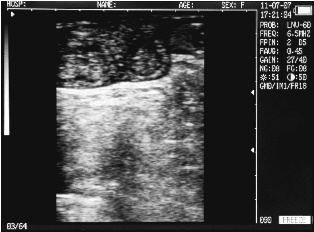

Uterine horn heifers